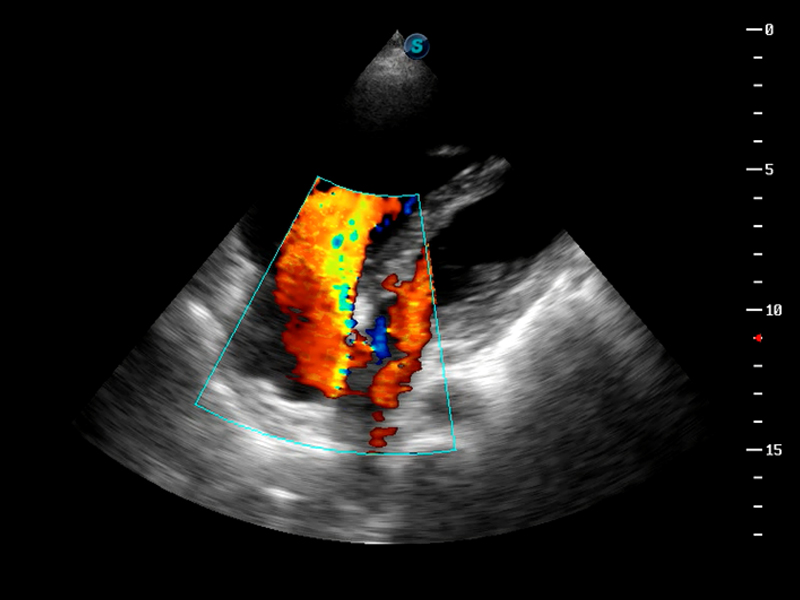

S9便携式彩色多普勒超声诊断仪是球速体育入口研发的高端便携彩超设备,外观设计新颖、产品性能卓越。S9在便携超声领域采用了突破传统的触摸屏交互设计,并以先进的软件硬件技术和设计理念,为您带来清晰的图像质量、稳定的工作性能和便捷的操作体验。

AutoC智能血流追踪